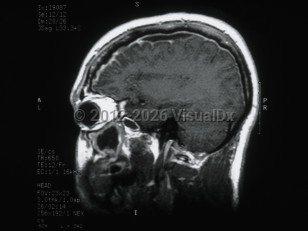

Subdural empyema

Subdural empyema is a collection of pus in the space between the dura and the arachnoid. Infection of the paranasal sinuses is a risk factor for cranial subdural empyema, as the infection can spread to the space by way of emissary veins. Contiguous spread of infection from osteomyelitis of the skull, meningitis, mastoiditis, or otitis media are also possible. Other etiologies include trauma, seeding of an existing subdural hematoma, or postoperative infection. These infections are typically polymicrobial.

Hematogenous seeding of the space is more likely to result in spinal subdural empyema. This location is less common, accounting for less than 5% of subdural empyema. Staphylococcus aureus is often implicated in infections in this location. Patients may present with fever, headache, and altered mental status (or some combination of these symptoms). Focal neurological signs and seizures may also be present. Magnetic resonance imaging (MRI) with contrast is the diagnostic test of choice.

Treatment is with a combination of surgical decompression and antibiotic therapy. Complications include cerebritis, cerebral abscess formation, and venous sinus thrombosis. Morbidity and mortality in subdural empyema is directly related to delay in therapy.